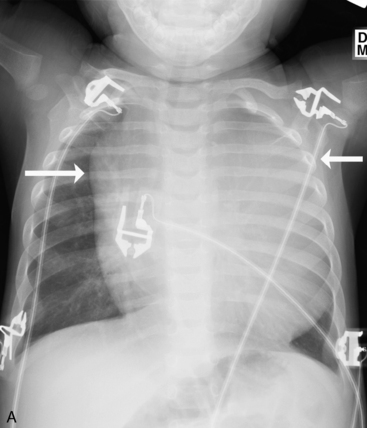

Children older than 6   years have mediastinal structures comparable to those of adults. The thymus shadow, seen in the upper third of the chest at the mediastinum, has bilateral lobes. The thymic silhouette blends almost imperceptibly with the cardiac silhouette, because it occupies contiguous space, giving the appearance of a widened mediastinum. It can produce a triangular shadow, resembling the sail of a boat (called the sail sign). The thymus is most often visualized on the chest radiograph from birth to 2   years of age, but may persist up to 5   years of age6,16,17,25 (Fig. 10-9).

image image

Fig. 10-9 Normal thymus. A, This supine anteroposterior film demonstrates the right lobe of the thymus projecting over the right upper lung field, creating the appearance of a widened mediastinum. The triangular shape (arrows) is the classic appearance of the sail sign (the right lobe of the thymus forms a triangular shape characteristic of the sail of a boat). B, This infant has a pneumomediastinum that has elevated the right and left lobes of the thymus (arrows) off the heart.

(B, Courtesy Sharon Stein, Nashville, TN.)